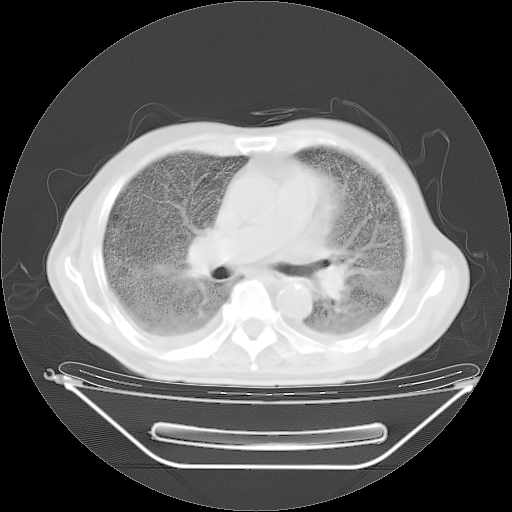

今天复查肺部CT,发现双肺广泛磨玻璃样改变。所以我把3月19日和5月9日相隔50天的肺部CT上传。请大家会诊。

2009年3月19日肺部CT片。

2009年3月19日肺部CT